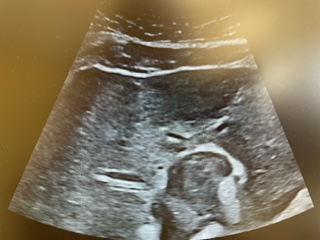

Descripción de los hallazgos ecográficos y las imágenes más relevantes para la resolución del caso

Realizamos POCUS en consulta y objetivamos líquido libre abdominal, así como hígado heterogéneo con distorsión grosera del parénquima, donde se objetivan dos lesiones hipoecogénicas de menos de 2 cm de longitud.